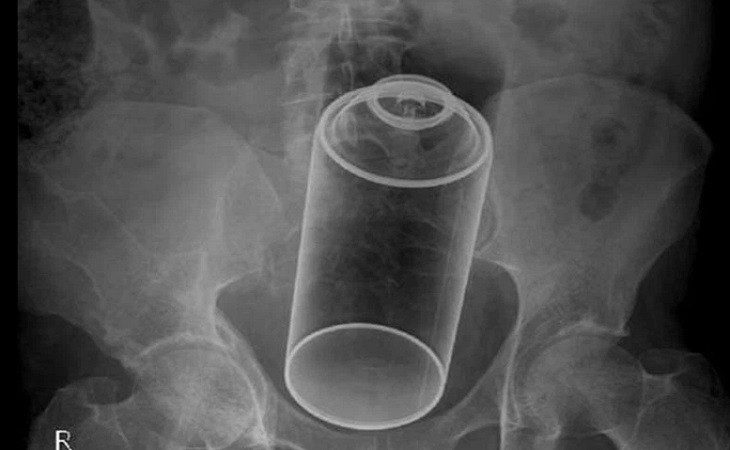

Врачи из разных стран поделились рентгеновскими снимками, на которых в анальных отверстиях людей запечатлены различные предметы. Об этом сообщает The Sun.

Медики рассказали, что за годы работы в больницах им приходилось доставать множество странных предметов из кишечников пациентов, среди которых: ветвь яблони, бокалы для шампанского, огурец, воронка, упаковка с таблетками, лампочки, зонтик и даже футляр с очками.

Но лидируют в данном списке, по понятным причинам, секс-игрушки. Один из врачей предложил продавать подобные вещи со специальными шнурами для удаления, чтобы облегчить труд медицинских работников. При этом доктора добавили, что секс-игрушки безопаснее, чем различные предметы из бытового обихода.